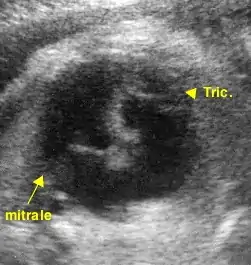

Le diagnostic peut être soupçonné sur l'incidence dite "des 4 cavités". Celle-ci permet d'analyser en particulier l'atrium et le ventricule gauches (OG - VG), l'atrium et le ventricule droits (OD - VD) et la position des valves mitrale (Mi) et tricuspide (Tr).

L'attention est attirée par une dilatation apparente de l'atrium droit et l'impossibilité de visualiser, comme normalement, un appareil valvulaire tricuspide "symétrique" de l'appareil mitral. Cet appareil tricuspide est en fait retrouvé dans le ventricule droit, plus ou moins proche de son apex (pointe). Il est souvent difficile à distinguer de la "bandelette modératrice" (ou trabécule septomarginale), structure musculaire physiologique traversant le ventricule droit.